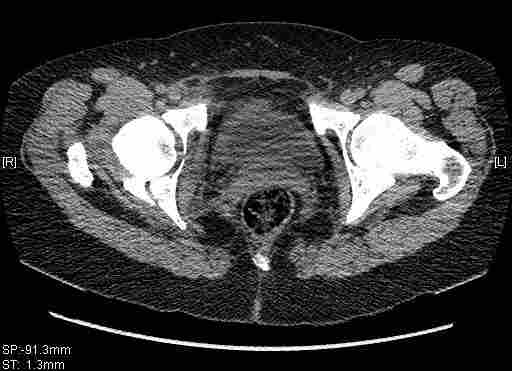

Re: Т-образный перелом вертлужной впадины

Удалось сегодня вывести пациентку в соседнюю больницу, где есть кт. Срезы сделаны только горизонтальные.